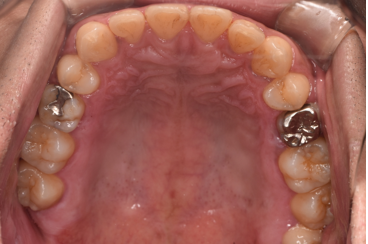

治療後

| 行ったご提案・治療内容 | 初診時に撮影したレントゲン、口腔内写真、歯周病検査の結果を用いて、歯周病治療の必要性をお伝えしました。 初診時は歯ブラシの使い方などセルフケアの方法をご説明し、その後に歯肉縁上歯石(歯肉より上に付く黄色または乳白色の歯石)を除去しました。 歯肉の炎症がある程度落ち着いた後日、再評価を行い、歯周治療へ移行しました。 |

| 術後の経過・現在の様子 | 経過は良好です。 |